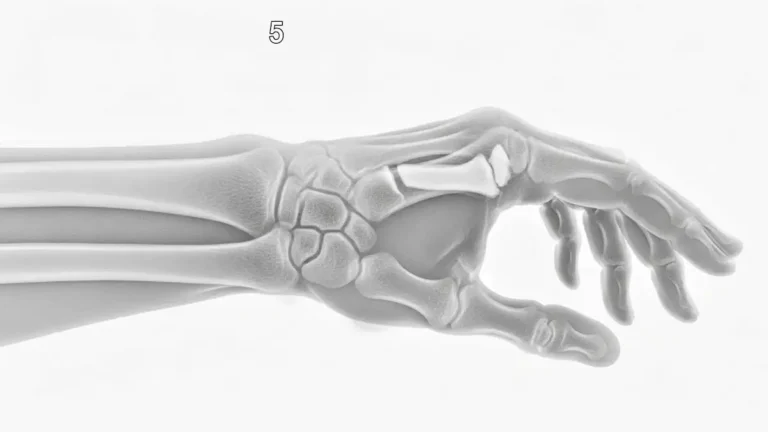

Fratura de boxer é o nome dado à quebra do colo do 5º metacarpo, o osso que liga o dedo mínimo ao punho. Ela costuma acontecer depois de um soco em superfície rígida, mas também pode surgir após quedas, pancadas…